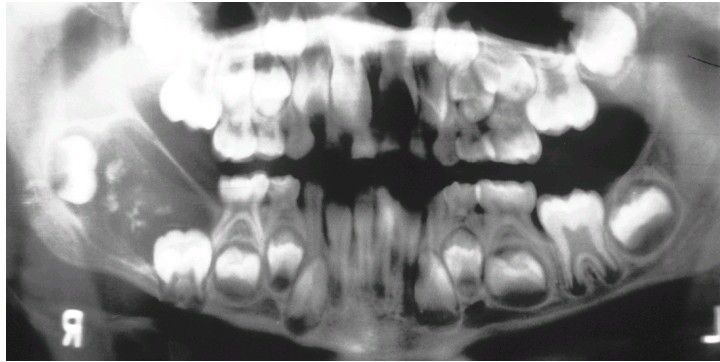

Ameloblastic Fibro-Odontoma

. Radiolucent defect in the ramus containing small calcifications having the radiodensity of tooth structure.